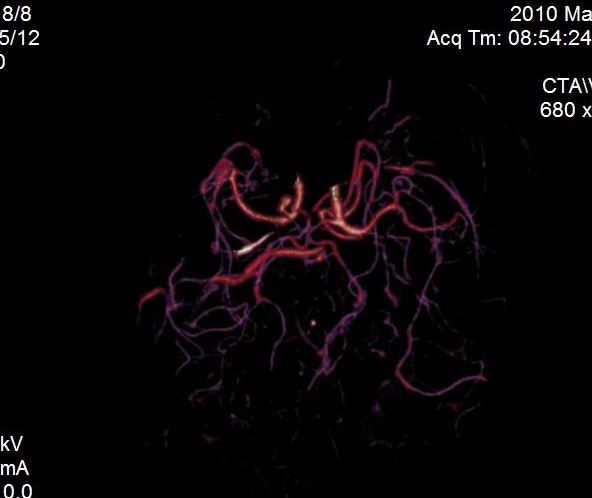

男.60岁,渐进性意识不清,ct检查双侧额颞顶部硬膜下血肿,开颅术后行脑血管cta,大脑中动脉起始部见一瘤状血管扩张。请各位老师留下宝贵意见

太常见了,报动脉瘤就可以

符合动脉瘤表现。

符合动脉瘤表现。

动脉瘤。

颅内动脉瘤。

后重建做得不是很好看,要将维蒂斯环充分显示,最好在增加一个mip。这样不好定位。

小动脉瘤

典型

符合动脉瘤的表现

动脉瘤

符合动脉瘤表现。

小动脉瘤

典型